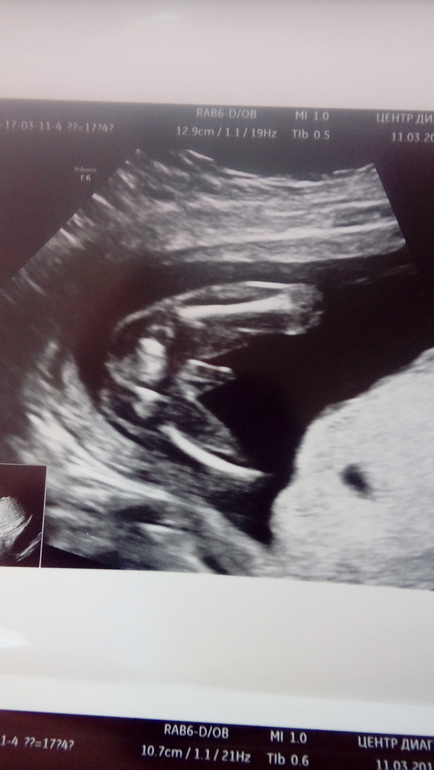

Наше узи после стационара

УЗИ, КТГ, доплерДела наши улучшились,шейка была 28 стала 33,то тонус еще есть и плацента низковато,но в целом все лучше!

И моя девочка превратилась в мальчика))))

Мужииикииииии))))